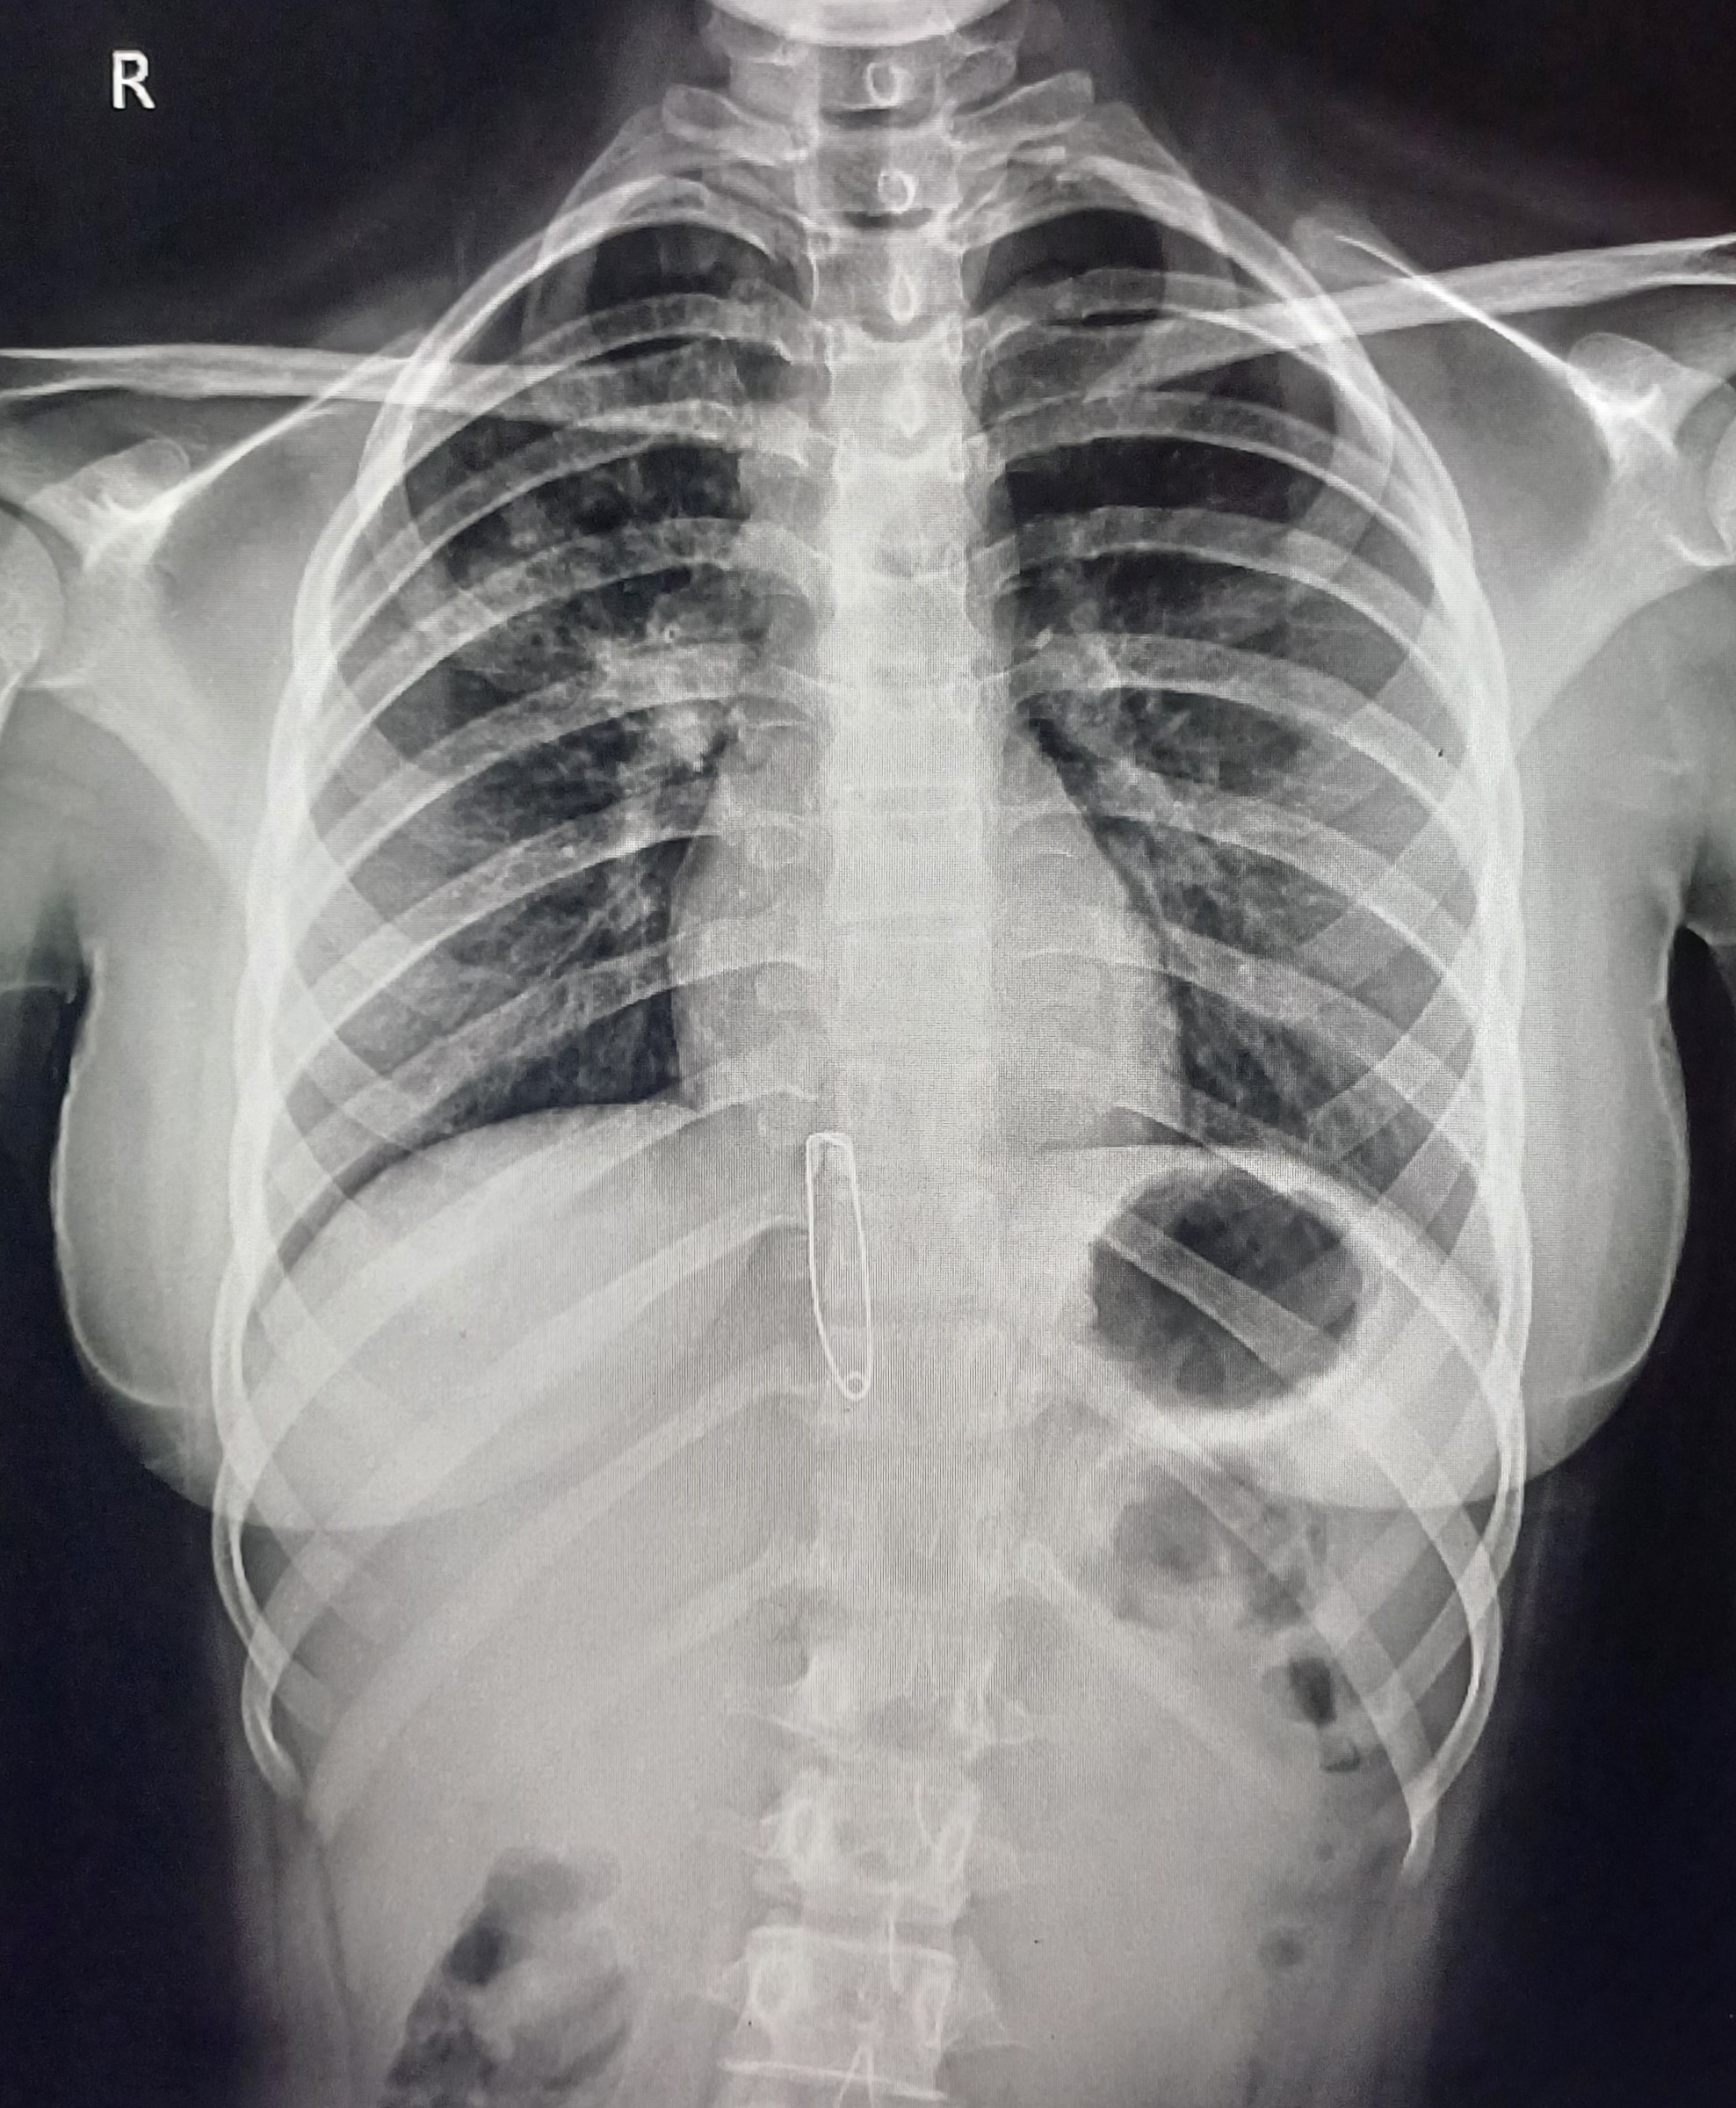

| 7 | IGGMC, Nagpur, Nagpur | P2 | 29-4465 | Ibrahim Pathan | Consent taken on Paper | 21 Yrs. |

Provisional Diag : Pleural Effusion ?

Final Diag : Tubercular Pleural effusion (Clinically Diagnosed Tubercular Pleural effusion) |

TB Case (Confirmed) | Right sided pleural effusion | Abnormality visible on x-ray |

View |